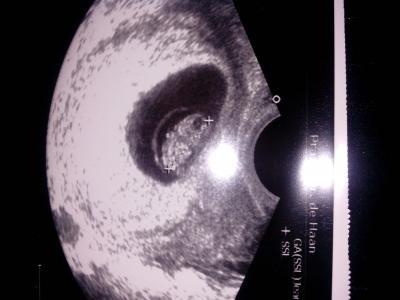

Mein Bauchbewohner. ...

Bild zu Mein Bauchbewohner. ... - Forum für April - Mamis

Super Neuigkeiten! & ein klasse Foto

Schönes Bild&525;&525; Wäre auch gern schon in der 10. Woche! Lg